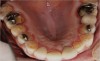

Figure  2  Loss of tooth surface surrounding amalgam and appearance of the restoration protruding from the tooth surface.

Figure 2

Characteristics of damage to tooth structures caused by acidity include wear on the occlusal surfaces of molars and a saucer shape on the cusps of molars (perimolysis).12 The erosion can vary from minor and subtle changes on the tooth surface, ie, loss of luster, a dull or matted look, to cupping on occlusal surfaces or incisal edges, which may extend to dentin. Usually, the erosive lesions demonstrate greater width than depth. When combined with abrasive forces or stresses, the tooth surface loss may occur at a faster rate (Figure 2, Figure 3, Figure 4 and Figure 5).